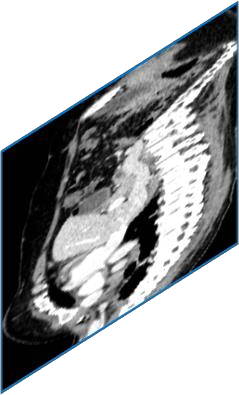

Due to the constraints of the imaging device and high cost in operation time, computer tomography (CT) scans are usually acquired with low intra-slice resolution. Improving the intra-slice resolution is beneficial to the disease diagnosis for both human experts and computer-aided systems. To this end, this paper builds a novel medical slice synthesis to increase the between-slice resolution. Considering that the ground-truth intermediate medical slices are always absent in clinical practice, we introduce the incremental cross-view mutual distillation strategy to accomplish this task in the self-supervised learning manner. Specifically, we model this problem from three different views: slice-wise interpolation from axial view and pixel-wise interpolation from coronal and sagittal views. Under this circumstance, the models learned from different views can distill valuable knowledge to guide the learning processes of each other. We can repeat this process to make the models synthesize intermediate slice data with increasing inter-slice resolution. To demonstrate the effectiveness of the proposed approach, we conduct comprehensive experiments on a large-scale CT dataset. Quantitative and qualitative comparison results show that our method outperforms state-of-the-art algorithms by clear margins.